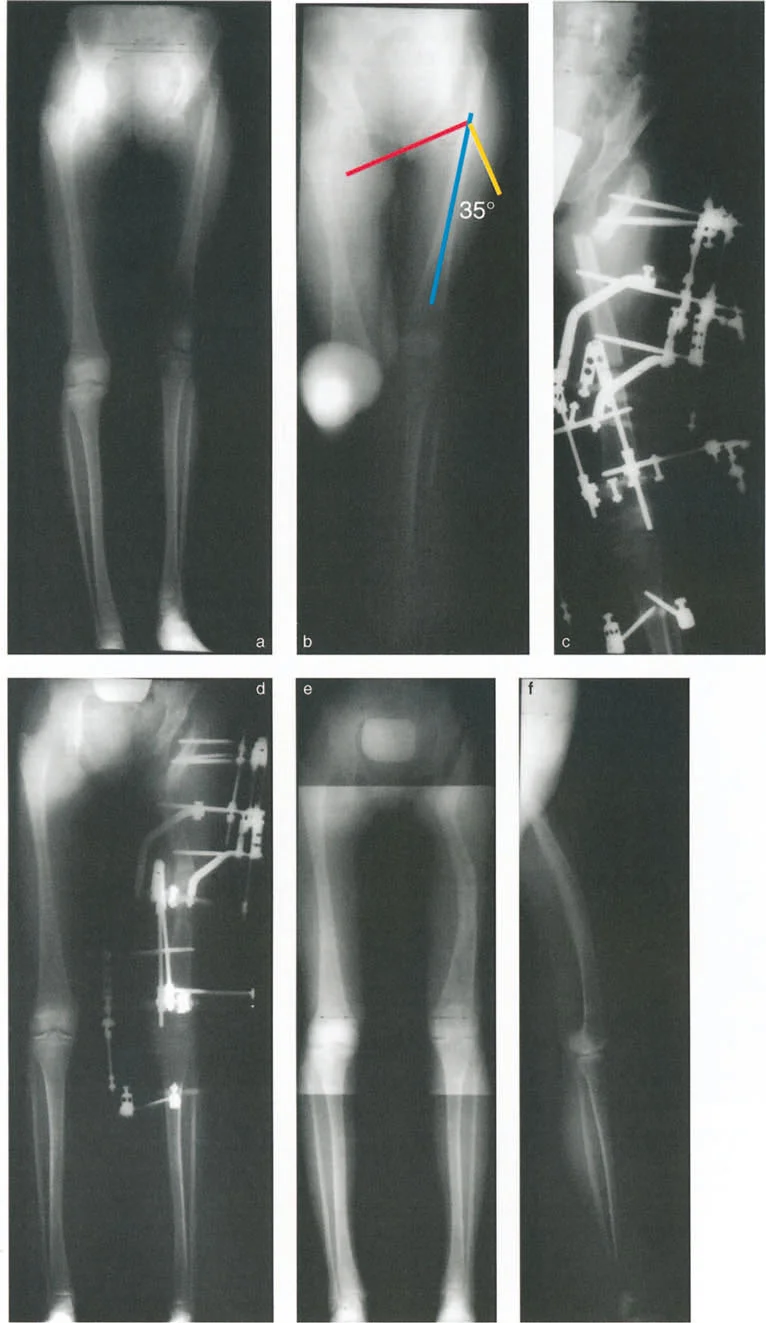

رسم توضيحي لتقييم ما قبل الجراحة لأقصى تقريب لعظم الفخذ (اختبار التقريب المتقاطع للساقين). في هذا المريض، تبلغ زاوية التقريب القصوى 45 درجة بالضبط.

صورة أشعة سينية بعد التخطيط توضح تنفيذ القطع العظمي القريب. تم تطبيق تصحيح تقوس خارجي بزاوية 60 درجة لتوفير دعم قوي للحوض والقضاء على هبوط الحوض.

تخطيط القطع العظمي القريب (العلوي):

* تحديد المستوى: يتم تحديده بدقة عند مستوى الحدبة الإسكية (Ischial Tuberosity) لتحقيق أفضل نقطة ارتكاز وسطية.

* تحديد زاوية التقوس الخارجي (Valgus): تُحسب باستخدام معادلة دقيقة: زاوية هبوط الحوض أثناء الوقوف على ساق واحدة + 15 درجة تصحيح زائد.

* تحديد الإزاحة (Translation): يتم إزاحة الجزء البعيد من العظم بمقدار نصف سمك العظم نحو الداخل لضمان التلامس العظمي المناسب والمحاذاة الميكانيكية.

تخطيط القطع العظمي البعيد (السفلي):

* رسم المحور الميكانيكي القريب الجديد (New PMA): خط عمودي على الخط الأفقي للحوض يمر عبر ثلث إلى نصف المسافة الجانبية للحافة الأنسية للجزء القريب.

* رسم المحور الميكانيكي البعيد (DMA): امتداد لخط المحور الميكانيكي لعظم الساق.

* تحديد مركز دوران التشوه البعيد (Distal CORA): نقطة تقاطع الخطين PMA الجديد و DMA هي المستوى الدقيق للقطع العظمي الثاني.

* تطبيق قواعد القطع العظمي: إذا كان مستوى التقاطع مرتفعًا جدًا، يمكن تحريك القطع العظمي للأسفل، ولكن يجب تعويض ذلك بإزاحة العظم نحو الداخل جنبًا إلى جنب مع التقوس الداخلي (Varus) لاستعادة المحور الميكانيكي، وفقًا لقاعدة بالي الثانية للقطع العظمي.